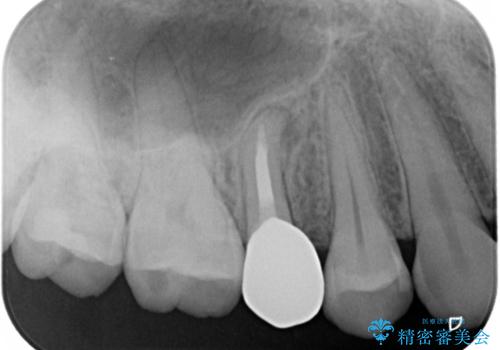

右上の被せものを除去したところ、中で歯が割れていたため、部分矯正で引っ張り出すことになりました。

・約3か月ほど引っ張り出します。

・十分に引っ張り出した後、歯肉の手術が必要となります。

・歯肉が落ち着いてから最終的な被せものの製作となります(約3か月)。